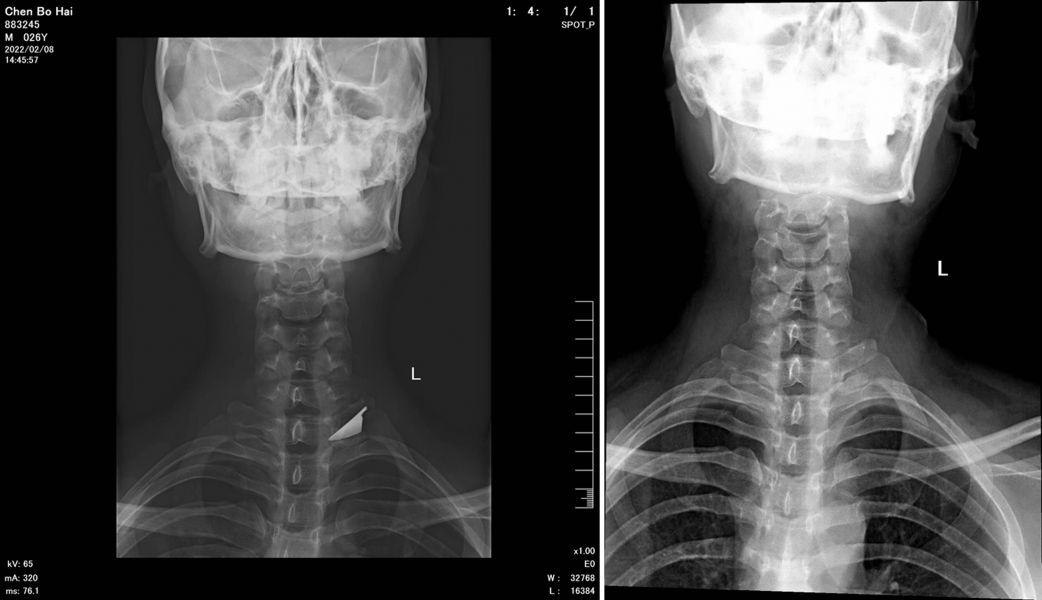

该患者10余年前因意外致左侧颈部被水果刀刺入,断裂的刀刃遗留于颈部颈椎旁,然而运气使然,这枚神奇的刀刃避开了颈动脉、颈静脉、臂丛神经、椎动脉等重要的组织,留存于颈部深处。没有致命这是幸运的,然而时隔多年,再要取出刀刃,手术难度则增加了1倍不止。

“悬颈之刃”术前、术后对比图